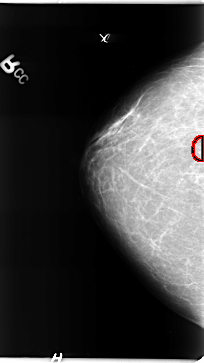

FILE: B_3136_1.RIGHT_CC.OVERLAY

TOTAL_ABNORMALITIES 1

ABNORMALITY 1

LESION_TYPE CALCIFICATION TYPE PLEOMORPHIC DISTRIBUTION CLUSTERED

ASSESSMENT 4

SUBTLETY 4

PATHOLOGY MALIGNANT

TOTAL_OUTLINES 1

BOUNDARY

RIGHT_CC LINES 4712 PIXELS_PER_LINE 2640 BITS_PER_PIXEL 12 RESOLUTION 50 OVERLAY